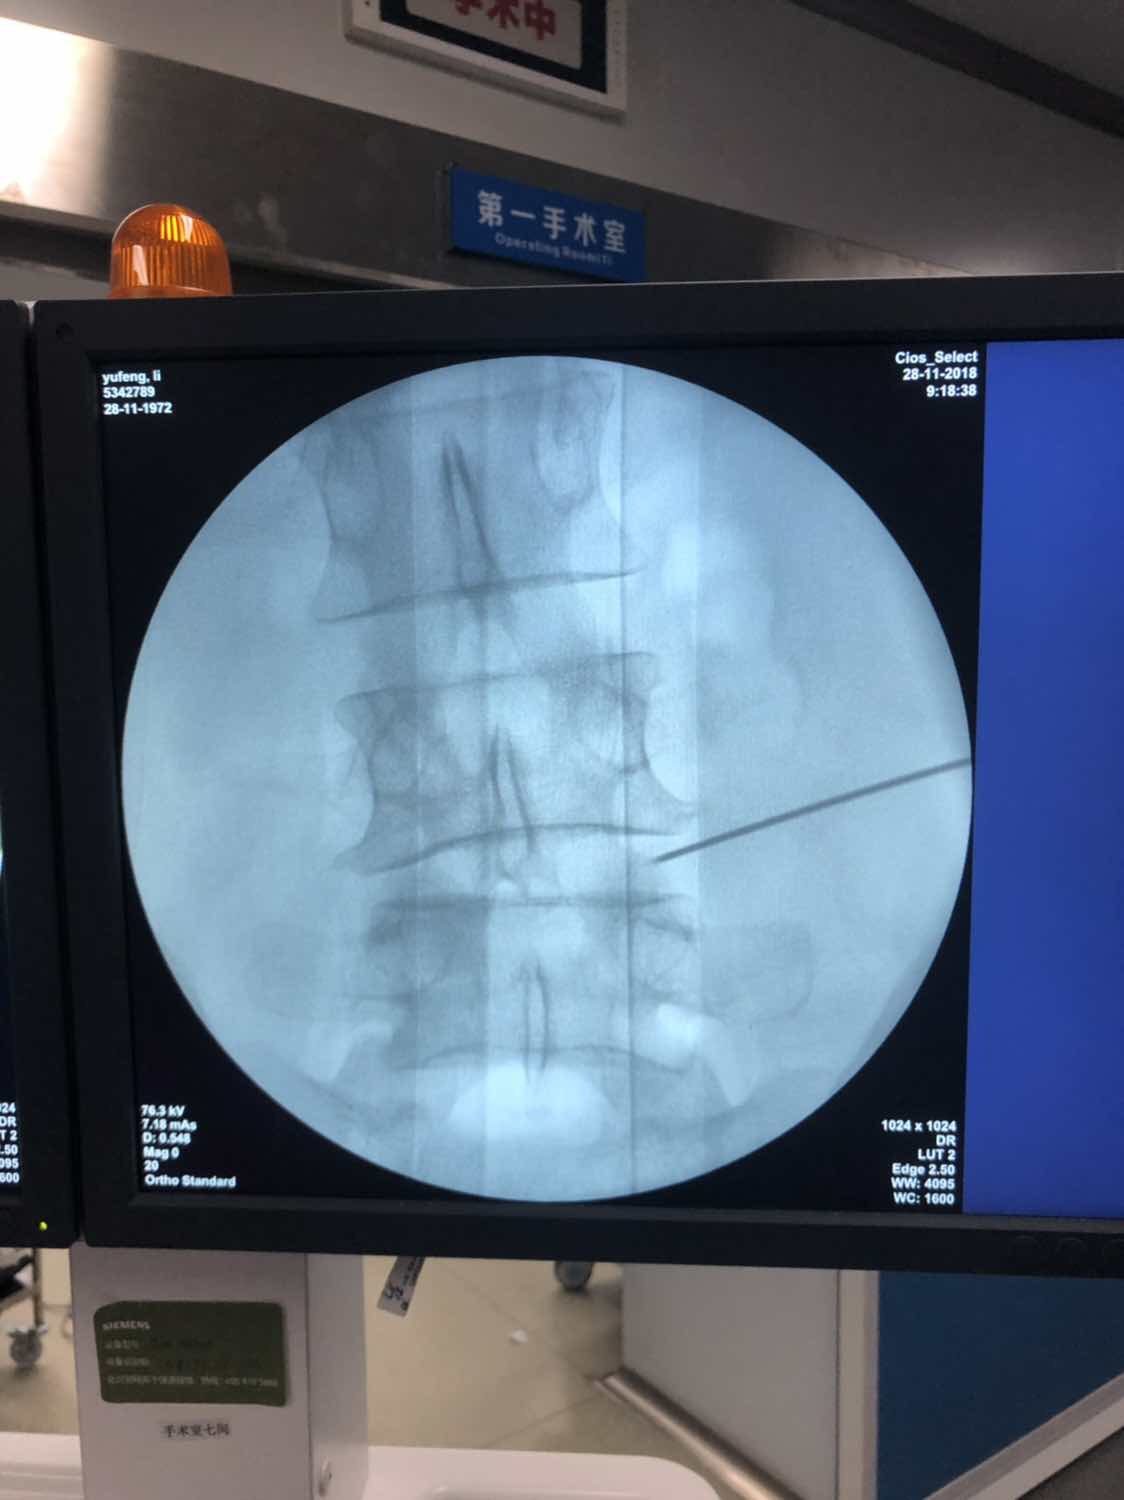

根据病情建议微创手术治疗。患者及家属知情同意,做术前准备。行左侧腰4-5椎间孔镜髓核摘除术。

术前腰椎保护性侧弯。

术后给予预防感染,预防血栓,预防应激性溃疡,消肿、营养神经、对症治疗。该患者术后恢复良好。患者左侧直腿抬高试验(-),腰部VAS平分2。病情稳定后出院。嘱患者:1.注意休息,避免劳累。2.适当行腰部周围肌肉功能康复锻炼。3.病情变化随诊。目前对于椎间盘突出的微创手术治疗方法主要有:椎间孔镜髓核摘除术,或并纤维环缝合,臭氧消融,髓核溶解术,射频消融,等离子技术。医生应结合患者的病情,选择合适的术式。该微创手术治疗的主要技术在于C臂下定位精准,熟悉解剖结构,这就要求临床医生具有较高的影像定位技术。